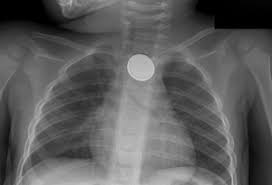

Button batteries pose a special risk in children, as they cause an alkaline reaction, and can result in serious internal burns. In the United States, a child swallows a button battery every 3 hours!

Ingested button battery in child: